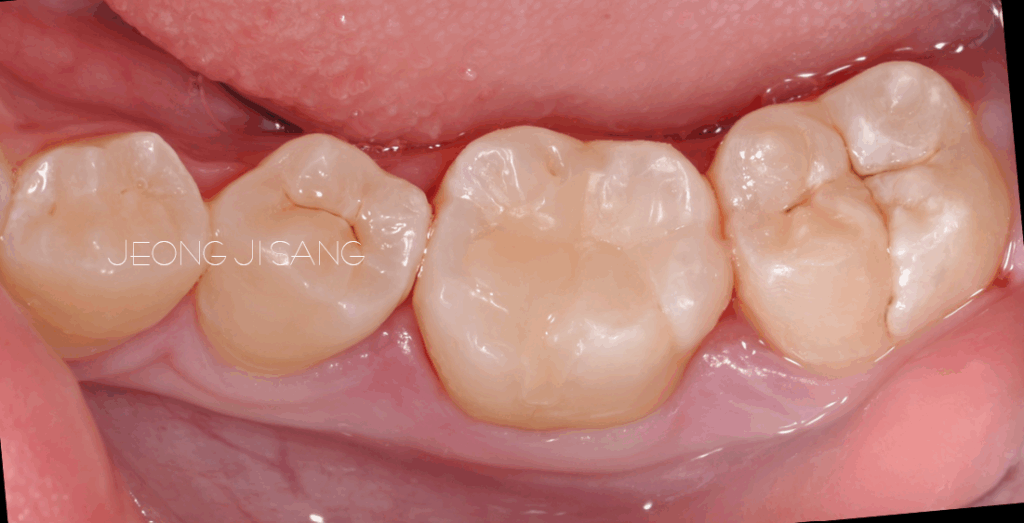

초진사진입니다. 사진을 보면 오래 전 케이스라는 것을 알 수 있습니다.

좌측 아래 첫번째 큰 어금니에 보험되는 재료인 지아이로 충전되어있는 것을 알 수 있습니다.

기존 치과재료를 다 제거하고 레진으로 치아의 형태를 하나씩 쌓아서 만들어 완성합니다.

오래전 케이스이긴 하지만 그 당시에도 치아의 형태를 비교적 잘 재현했었네요.